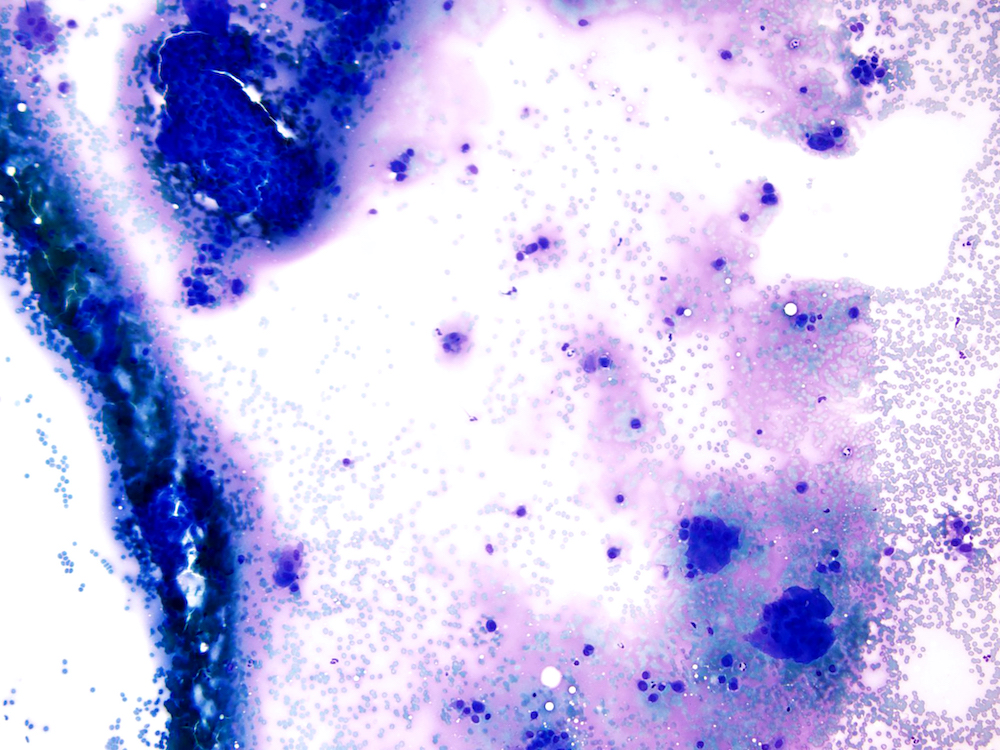

Cytology description

- FNA demonstrates clusters of uniformly round to oval cells with loose matrix and scattered multinucleated giant cells (Cancer Cytopathol 2018;126:552)

- H3.3B (H3F3B) p.Lys36Met (K36M): diffuse nuclear staining may be helpful to distinguish from aneurysmal bone cyst (Cancer Cytopathol 2018;126:552)